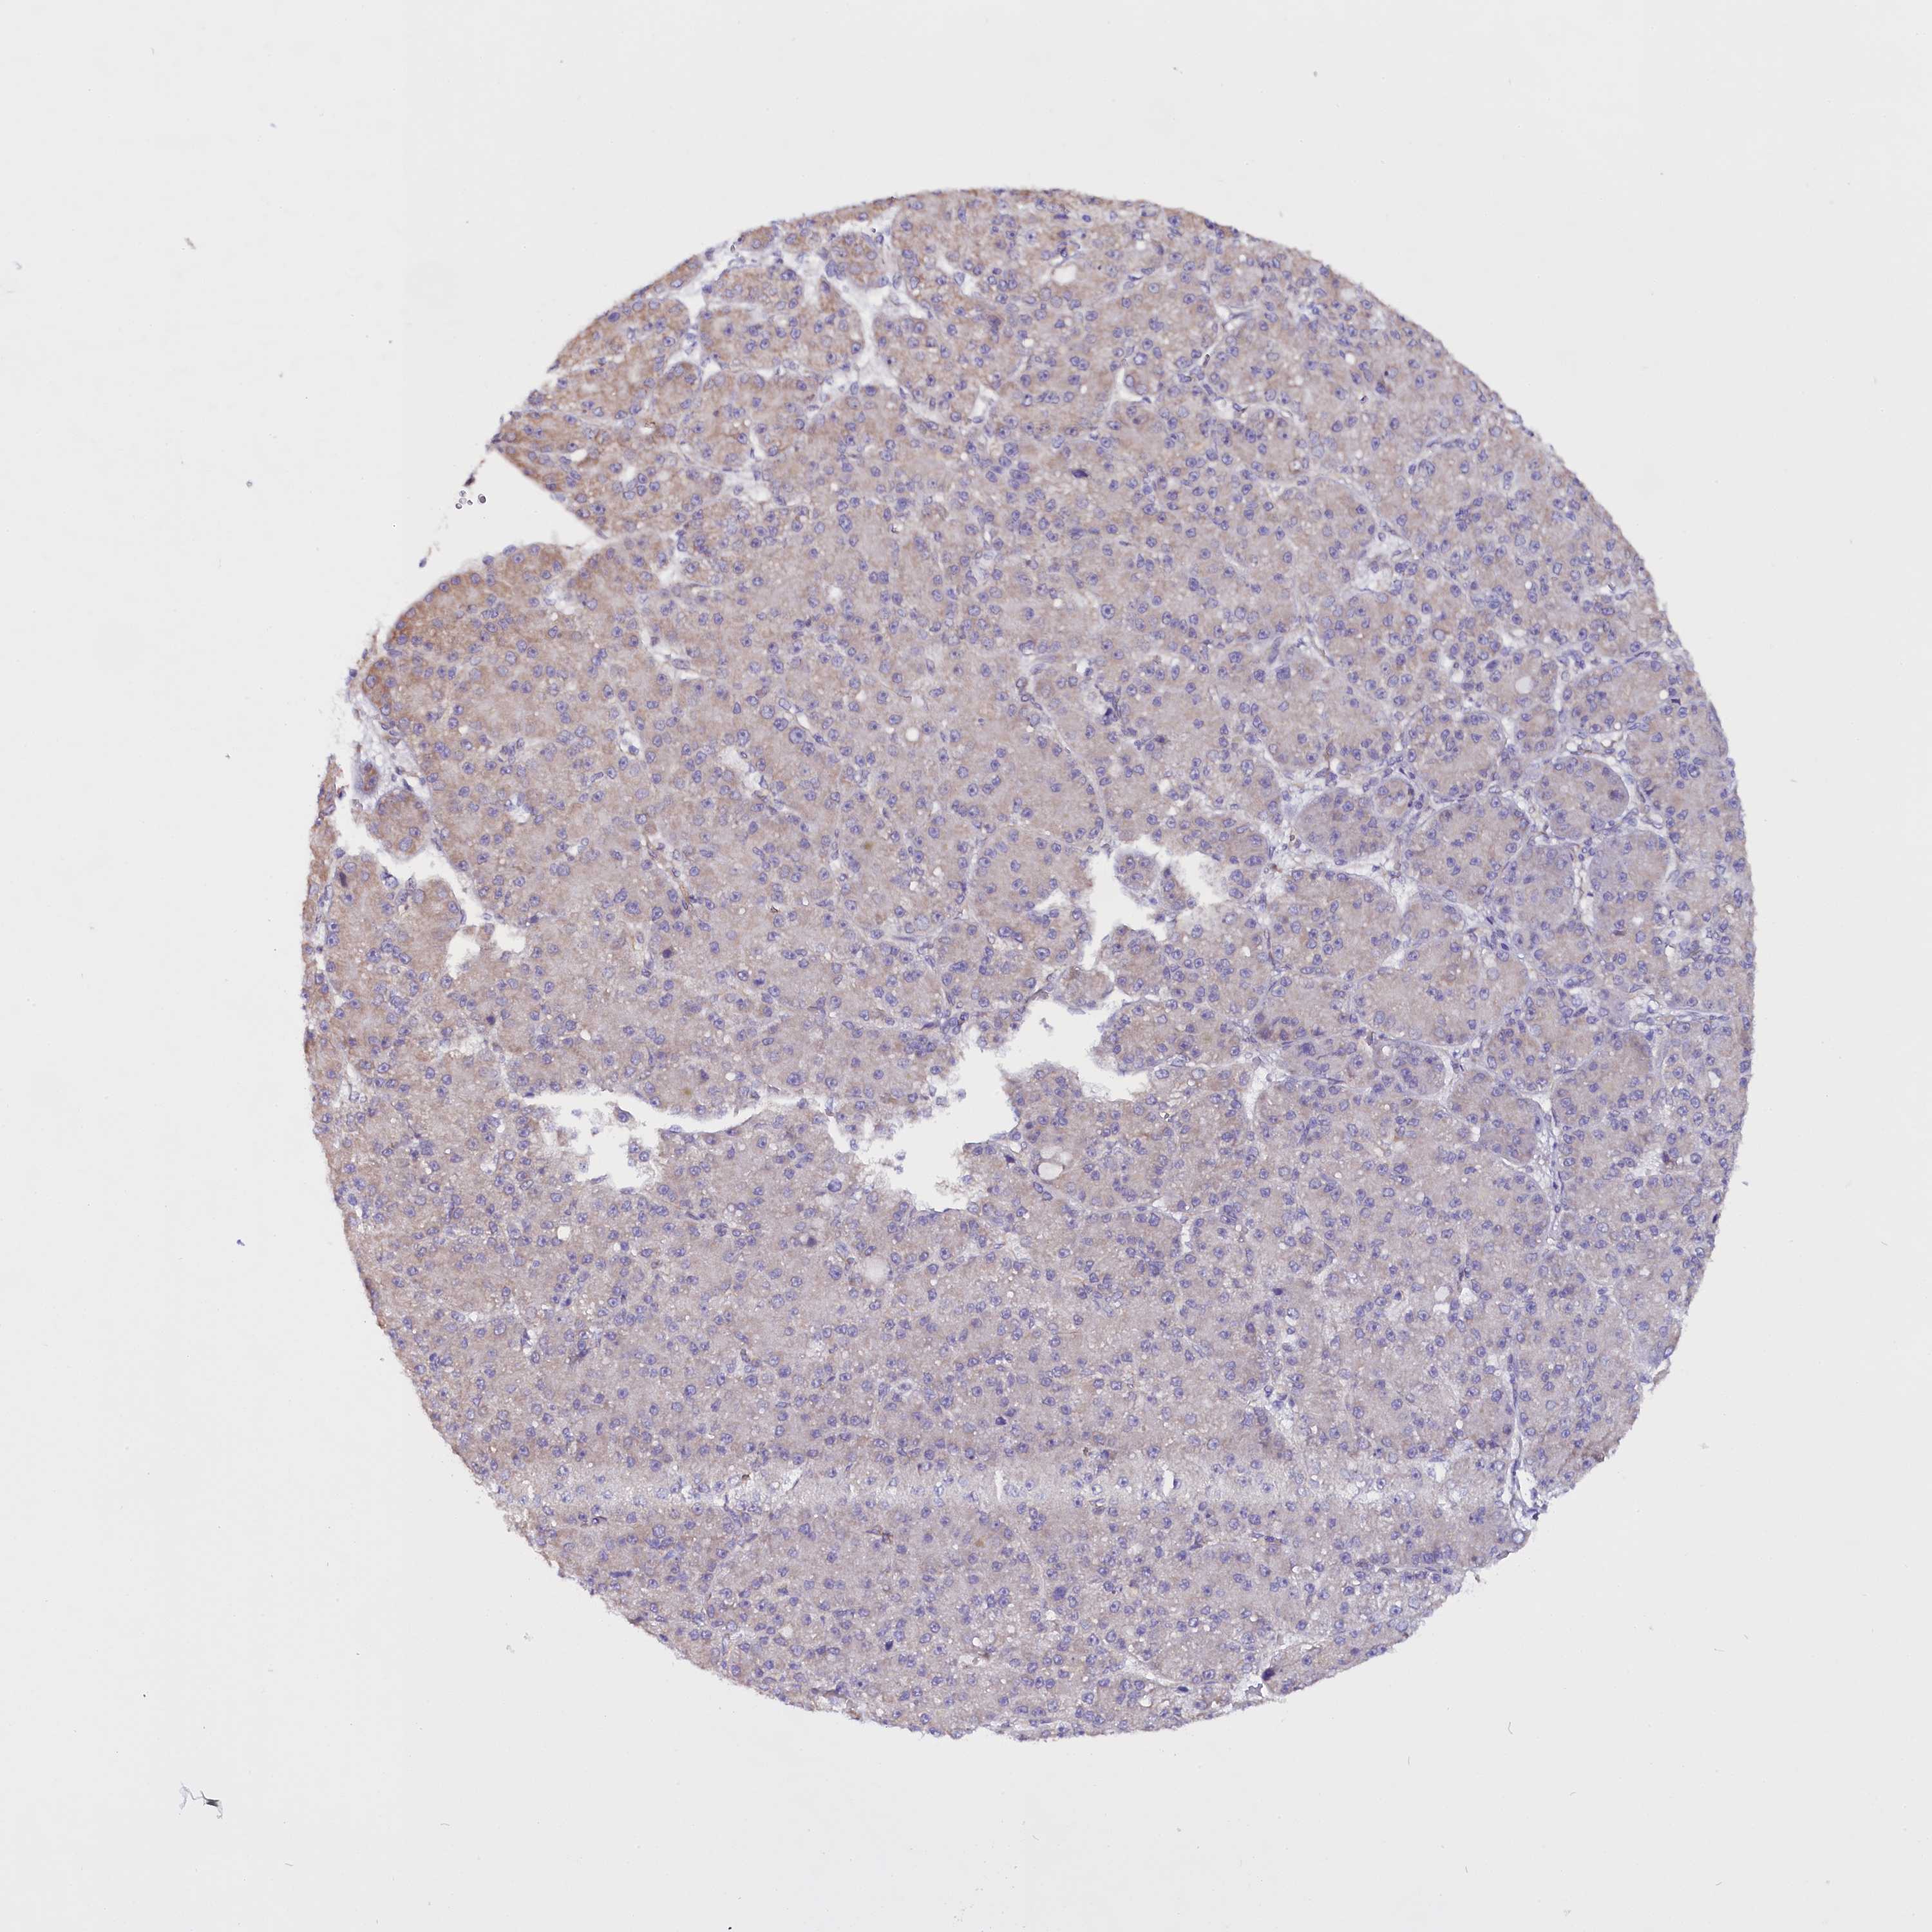

LIVER CANCER - Protein expressioni

A mouse-over function shows sample information and annotation data. Click on an image to view it in a full screen mode. Samples can be filtered based on level of antibody staining by selecting one or several of the following categories: high, medium, low and not detected. The assay and annotation is described here.

Note that samples used for immunohistochemistry by the Human Protein Atlas do not correspond to samples in the TCGA dataset.

Antibody stainingi

Antibody staining in the annotated cell types in the current human tissue is reported as not detected, low, medium, or high, based on conventional immunohistochemistry profiling in selected tissues. This score is based on the combination of the staining intensity and fraction of stained cells.

Each image is clickable and will lead to virtual microscopy that enables deeper exploration of all samples and also displays staining intensity scores, fraction scores and subcellular localization as well as patient and tissue information for each sample.

Antibody HPA041412

Antibody HPA056006

Staining

High

Medium

Low

Not detected

Intensity

Strong

Moderate

Weak

Negative

Quantity

>75%

75%-25%

<25%

None

Location

Nuclear

Cytoplasmic/membranous

Cytoplasmic/membranous,nuclear

Cholangiocarcinoma

Carcinoma, Hepatocellular, NOS